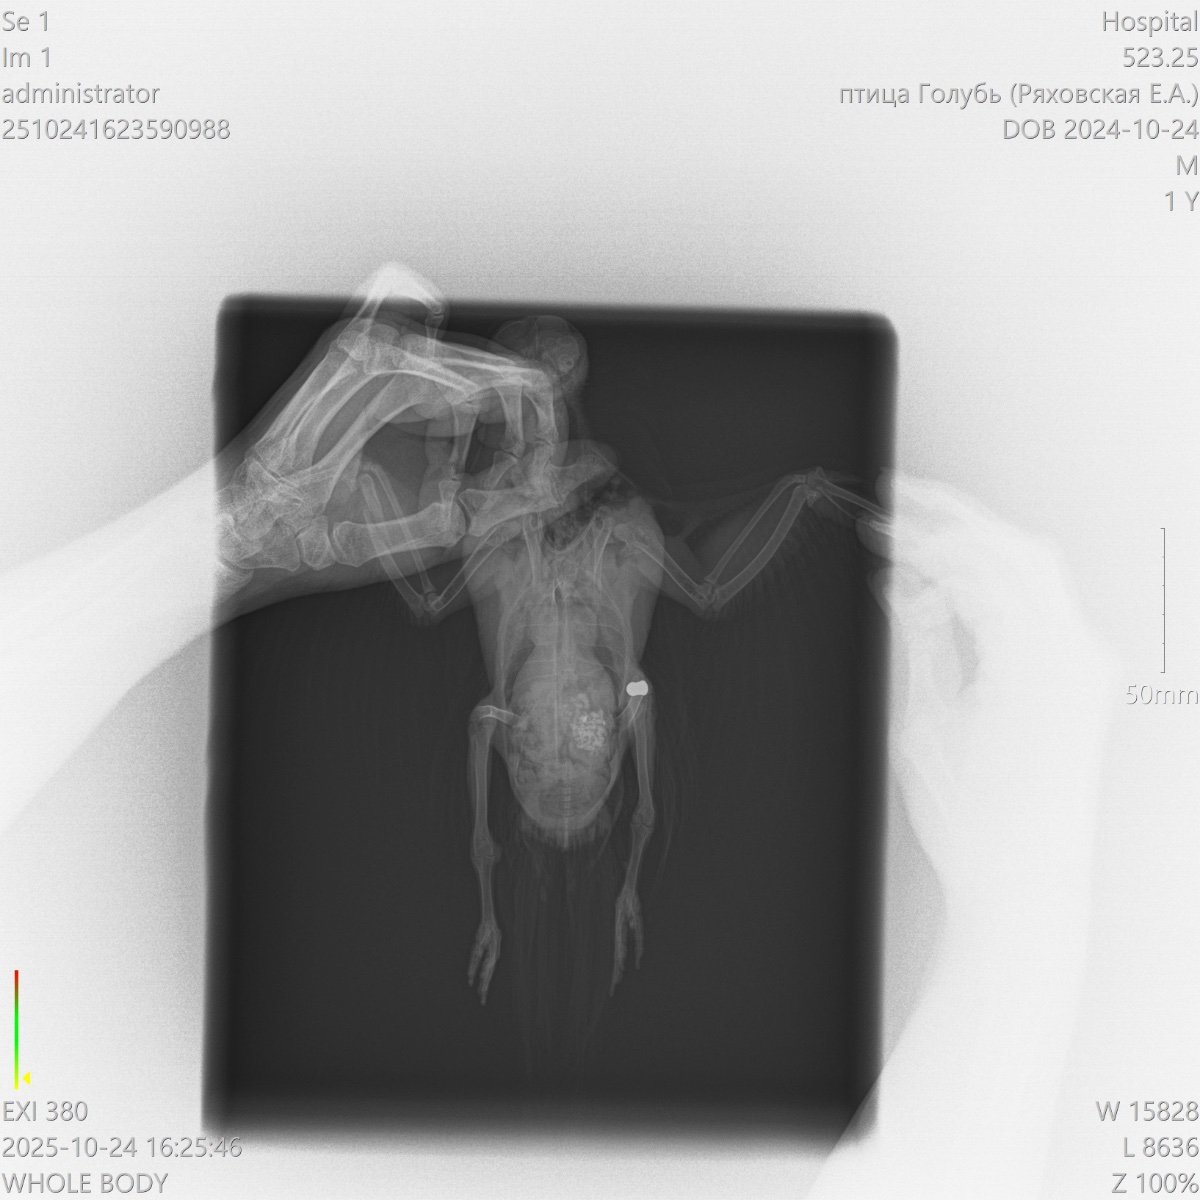

У голубя не функционируют лапки

Добрый день! Подобрали голубя, не встает на лапки, у нас в городе нет орнитолога, ветеринар не может точно сказать что с птицей. Помет зеленого цвета, кушает хорошо, перья блестят, очень активный.

Может ли это быть перелом позвоночника? Если да, то есть ли у птицы шанс встать на лапы?